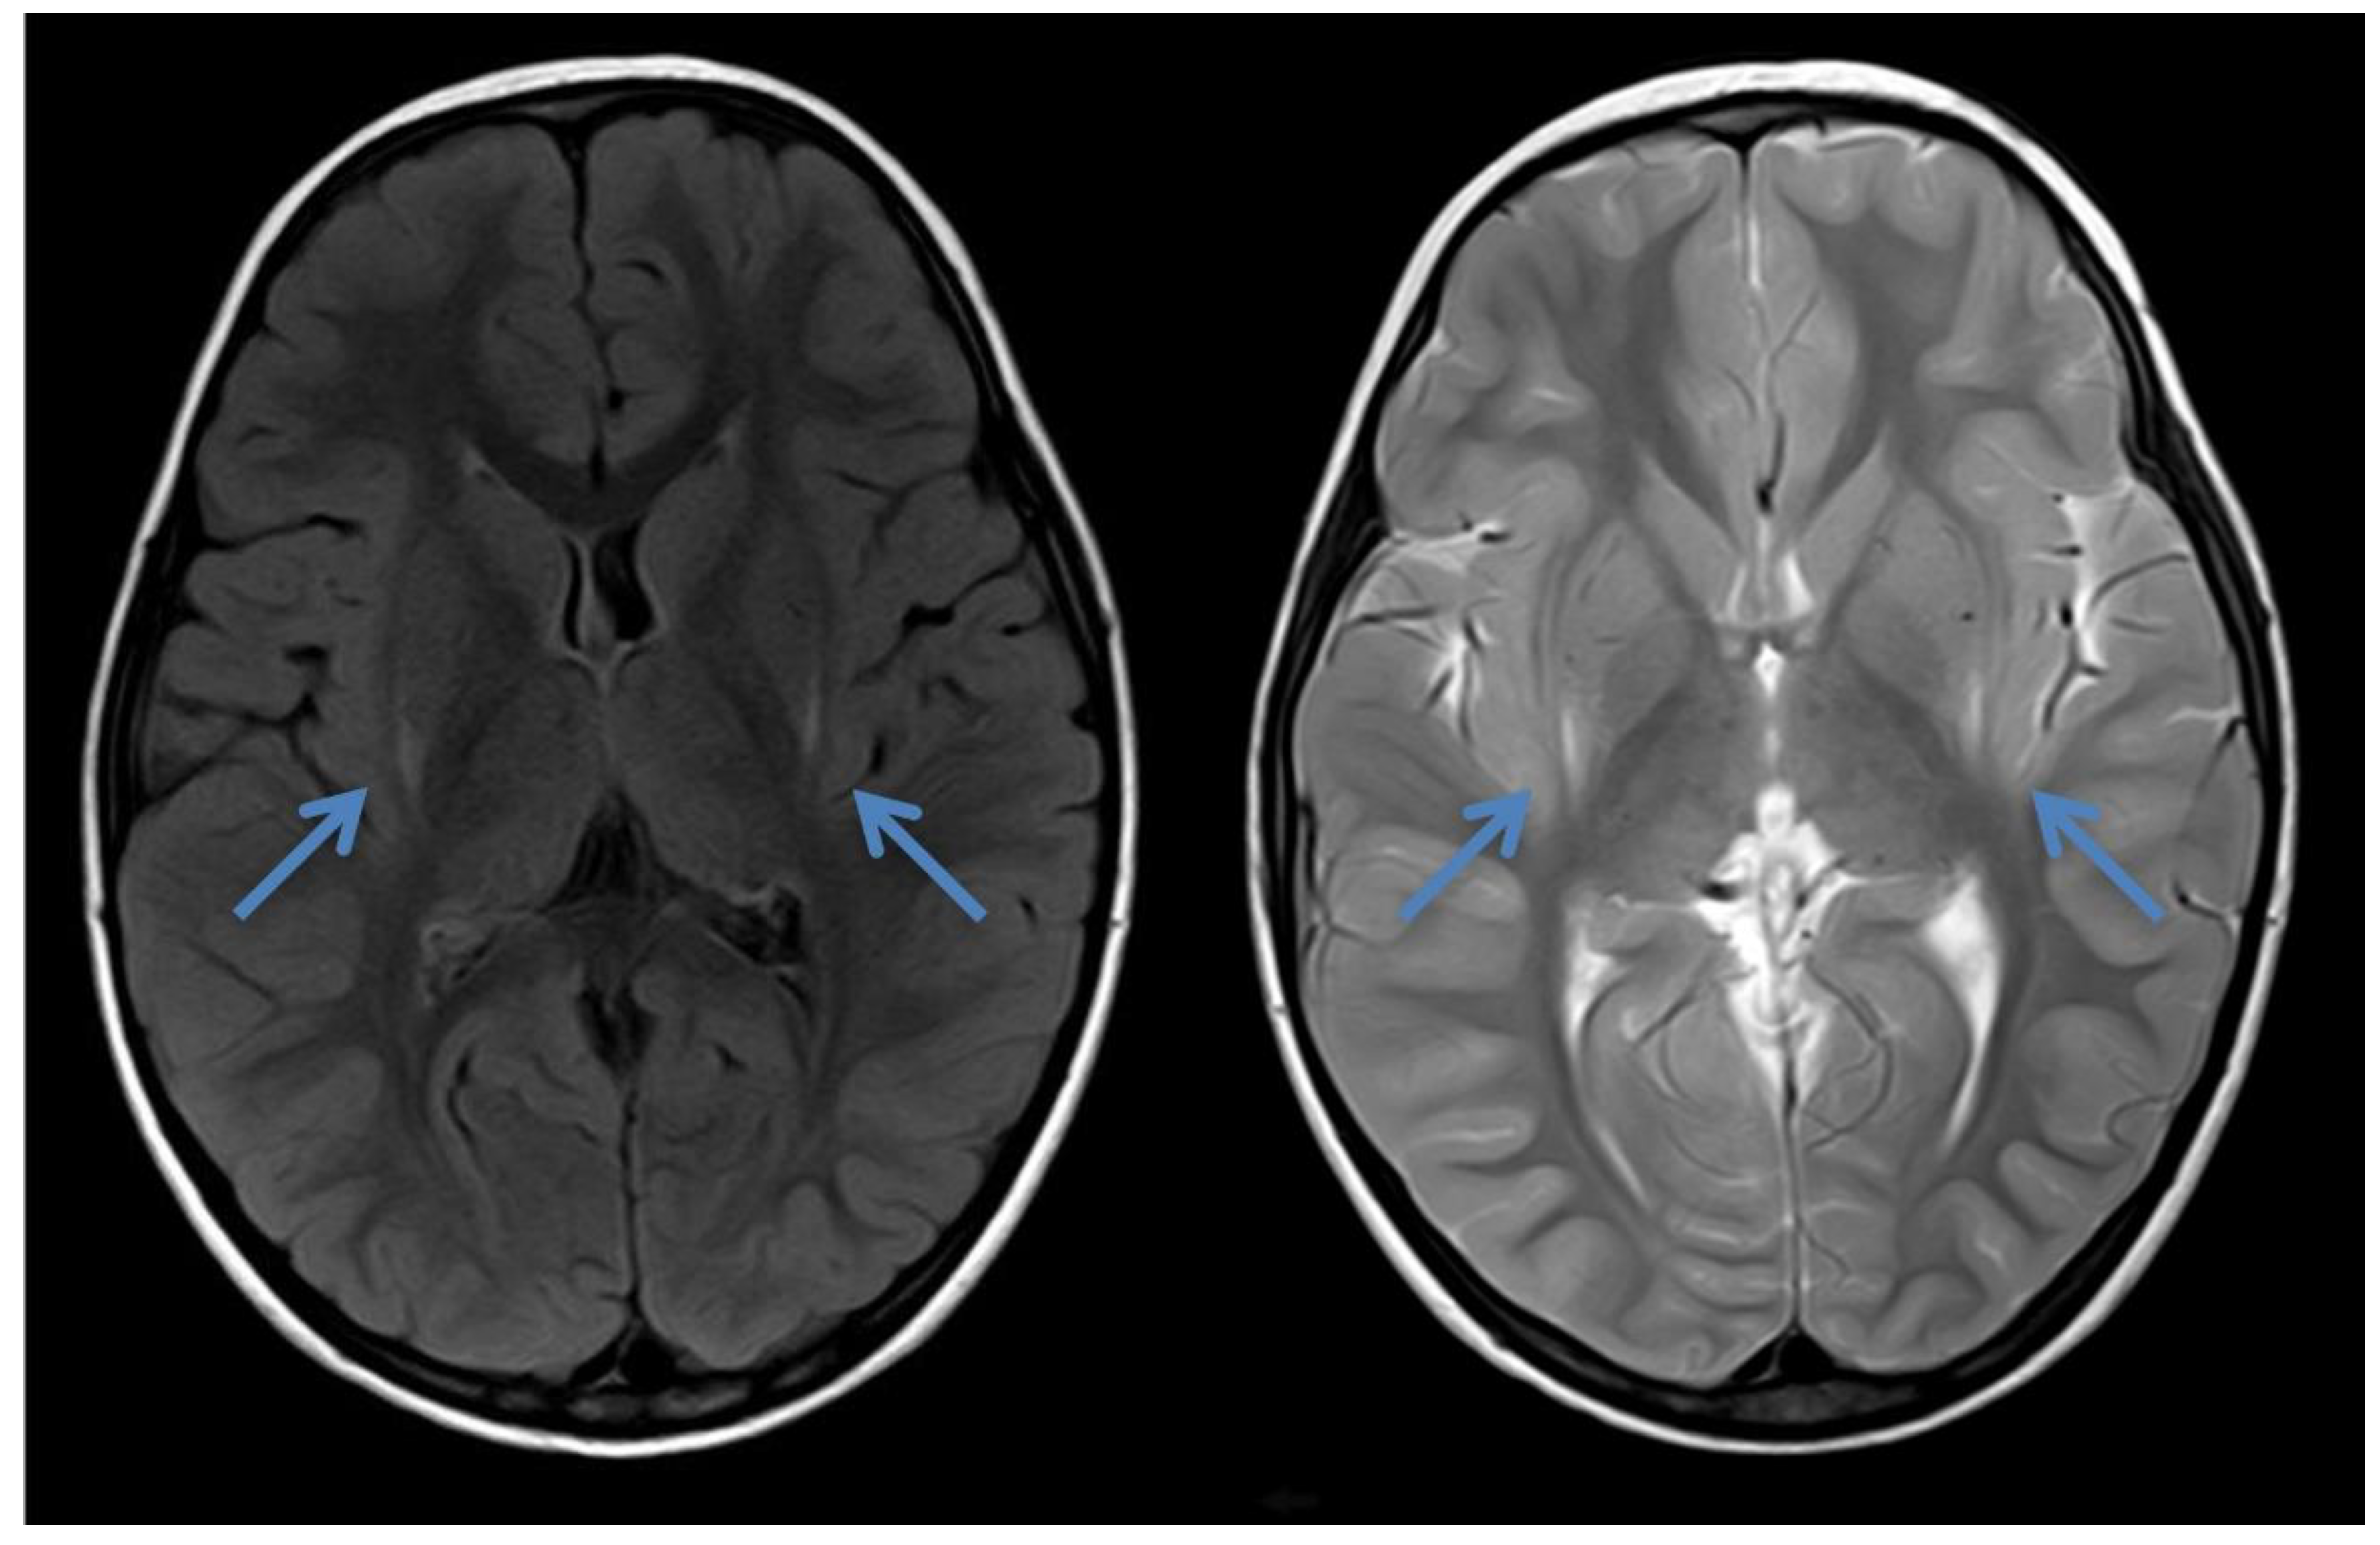

2.1. Case 1

2.2. Case 2

2.3. Case 3

2.4. Case 4